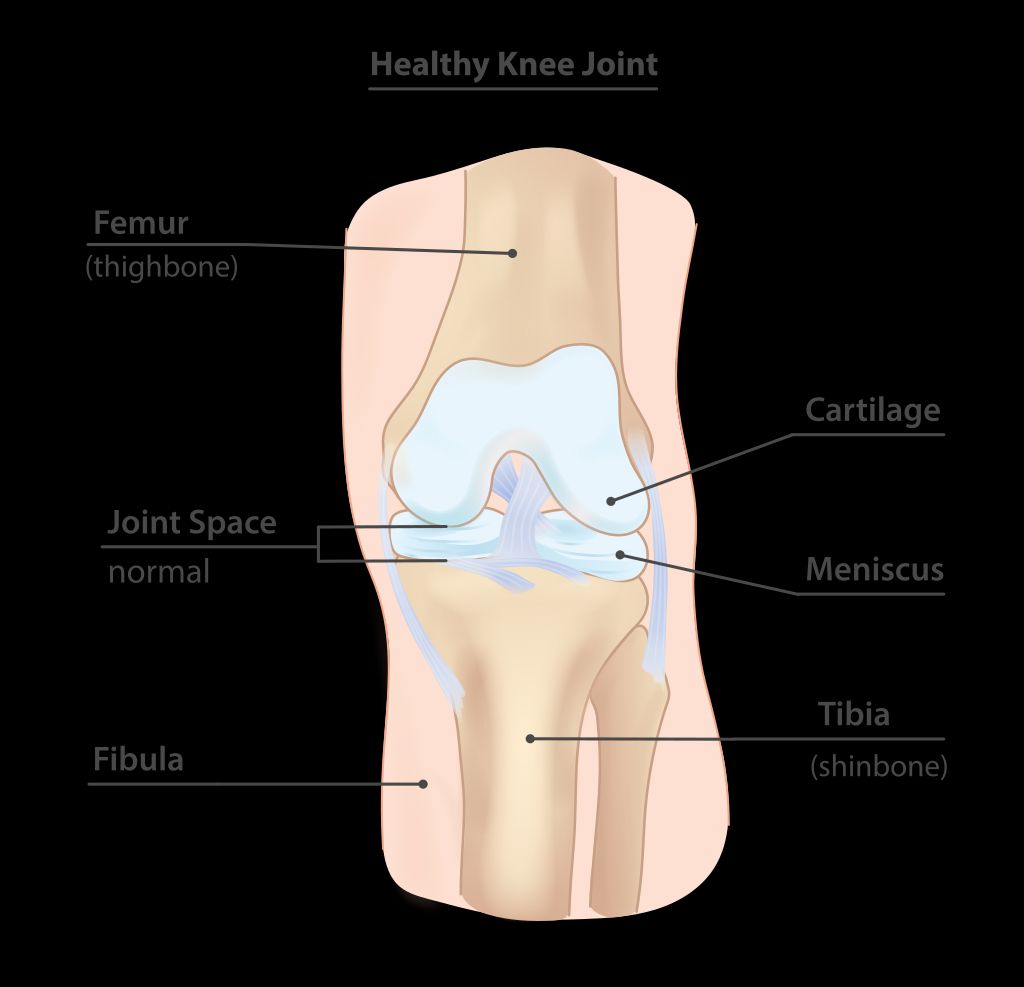

Anatomy of the Knee Joint

The knee joint is a complex structure that plays a crucial role in supporting our body weight and facilitating movement. Understanding the anatomy of the knee joint is essential for comprehending the mechanisms that can lead to anterior knee pain. The knee joint consists of the femur, tibia, and patella, all of which are connected by ligaments and surrounded by protective cartilage. This intricate arrangement allows for smooth and controlled movement, but it also makes the knee susceptible to various forms of stress and injury.

We understand the medial meniscus as a crucial component of the knee joint, primarily responsible for absorbing shock and stabilizing the joint during movement. Composed of fibrocartilaginous tissue, it is a C-shaped structure that conforms to the medial compartment of the knee, offering a cushion between the femur and the tibia.

The medial meniscus performs several vital functions, including:

• Load distribution: It evenly disperses the weight of the body across the knee joint.

• Joint lubrication: It aids in the reduction of friction between the articulating surfaces of the knee.

• Proprioception: It provides sensory feedback that helps in coordinating movement and balance.

The lateral meniscus, located on the outer edge of the knee joint, plays a vital role in distributing weight and reducing friction during movement. It works in conjunction with the medial meniscus to provide stability and cushioning to the knee. In a healthy knee, the lateral meniscus contributes to approximately 70% of the load-bearing capacity of the joint. This distribution of weight ensures that the knee joint remains stable and functional during various activities, including walking, running, and jumping. Maintaining the integrity of the lateral meniscus is essential for optimal knee function and overall joint health.

The knee joint is a complex hinge joint that allows for flexion, extension, and limited rotation. Articular cartilage covers the ends of the bones, providing smooth movement and cushioning. Ligaments, including the anterior cruciate ligament (ACL) and posterior cruciate ligament (PCL), provide stability and prevent excessive movement. The menisci, located between the femur and tibia, act as shock absorbers and enhance joint stability.

Structure Function

Femur Articulates with tibia and patella

Tibia Supports body weight and articulates with femur

Patella Protects knee joint and enhances leverage

Quadriceps muscles Extend the knee joint and stabilize the patella

Hamstring muscles Flex the knee joint and aid in hip extension